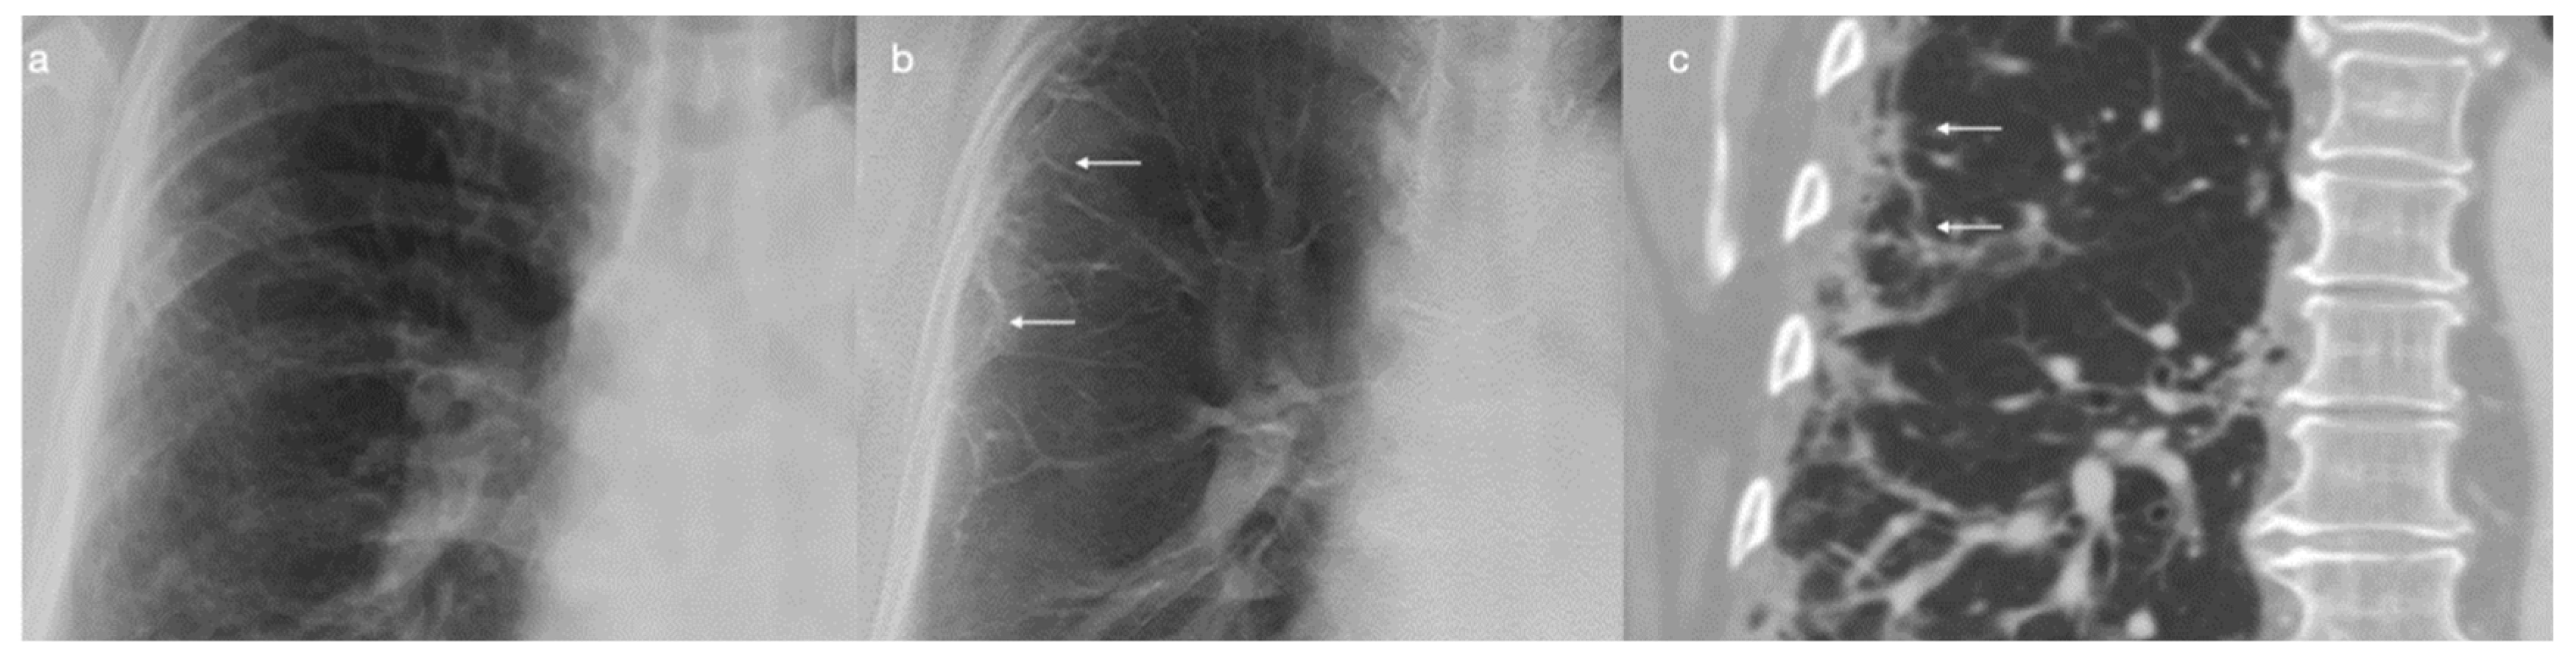

- Kruamak, T.; Edwards, R.; Cheng, S.; Hippe, D.S.; Raghu, G.; Pipavath, S.N.J. Accuracy of Digital Tomosynthesis of the Chest in De-tection of Interstitial Lung Disease Comparison With Digital Chest Radiography. J. Comput. Assist. Tomogr. 2019, 43, 109–114. [Google Scholar] [CrossRef] [PubMed]

- Quaia, E.; Baratella, E.; Cernic, S.; Lorusso, A.; Casagrande, F.; Cioffi, V.; Cova, M.A. Analysis of the impact of digital tomosynthesis on the radiological investigation of pa-tients with suspected pulmonary lesions on chest radiography. Eur. Radiol. 2012, 22, 1912–1922. [Google Scholar] [CrossRef]

- Vult von Steyern, K.; Björkman-Burtscher, I.; Geijer, M. Tomosynthesis in pulmonary cystic fibrosis with comparison to radiog-raphy and computed tomography: A pictorial review. Insights Imaging 2012, 3, 81–89. [Google Scholar] [CrossRef]